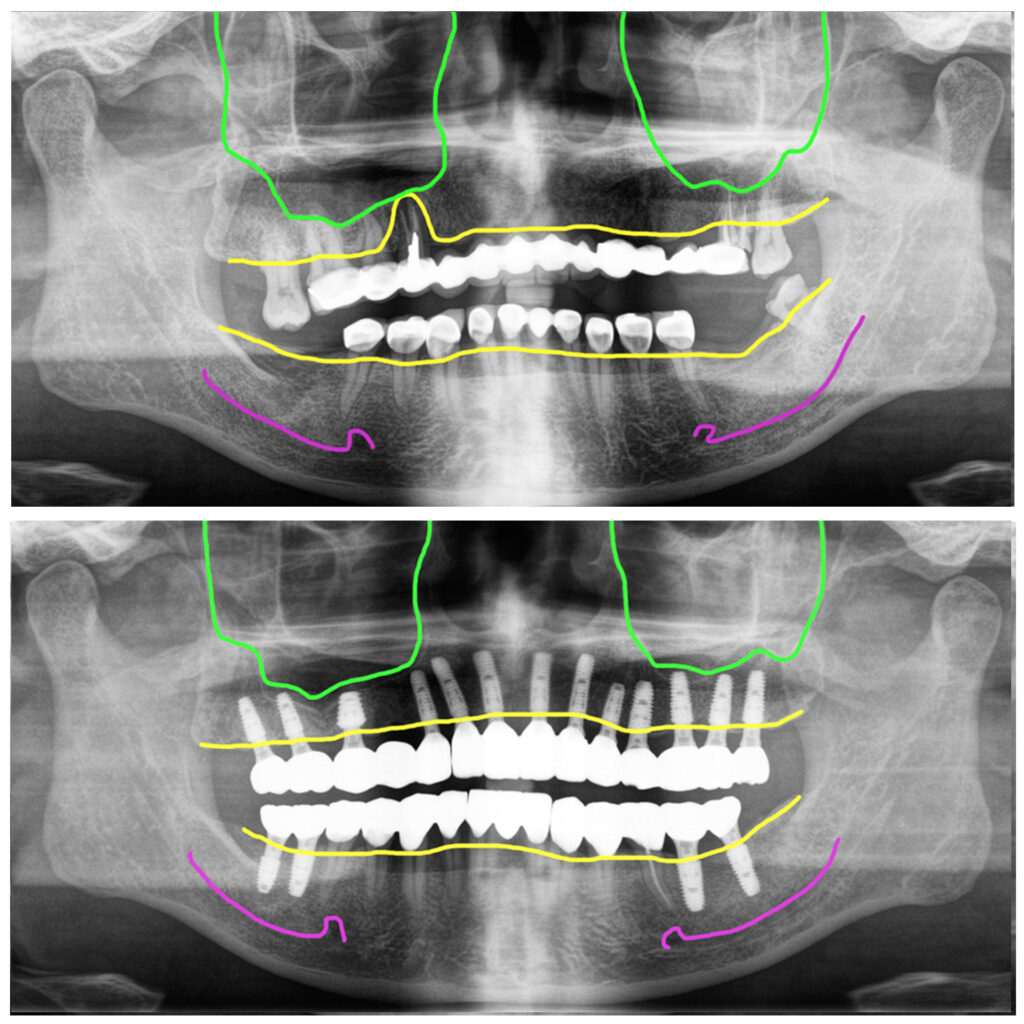

70대 중반의 어르신인데 엄청 건강하셨고, 텐션이 엄청 높은 분이셔서 더 기억이 납니다. 윗니에 다수의 치아가 없는 상태에서 임플란트가 아닌 긴 브릿지로 한 덩어리 보철을 하고 있었습니다.

롱브릿지 그러니까 여러개 연결이 되는 형태의 보철이 긴 경우 아무래도 보철의 움직임이 더 심하기 때문에 보철 속의 세멘트가 더 잘 녹습니다. 그래서 이렇게 긴브릿지 치료를 하신 분들에게서 자주 나타나는 현상이 세멘트가 녹고 나서 그 속에 있는 치아가 모두 썩는 현상입니다.

이 분도 브릿지를 제거했을 때 대부분의 치아들이 썩어 있어 모두 제거를 했고, 오른쪽에 한개 남아있는 치아는 아래로 너무 떨어져 이용할 수 없어 제거를 같이 했습니다.

아래는 보철이었지만 롱브릿지가 아니어서 속에 치아들이 썩지 않아서 다시 크라운 치료를 하는 식으로 치료를 진행하기로 했습니다.

위13개, 아래4개 즉시 식립

위쪽에 염증이 너무 심한 치아 자리 한 군데만 제외하고 모든 부위에 해당하는 치아개수대로 임플란트를 식립했어요.

뼈상태는 양호하신 편이었고, 발치와 동시에 즉시 식립해서 초기고정도 좋았습니다. 위에는 10개의 임플란트에 지대주를 연결해서 수술당일 임시치아를 해 드렸고, 아래는 보철을 제거한 부위의 치아들을 임시치아로 하고 양쪽어금니부위에 심은 임플란트는 임시치아 적용을 하지 않았습니다.